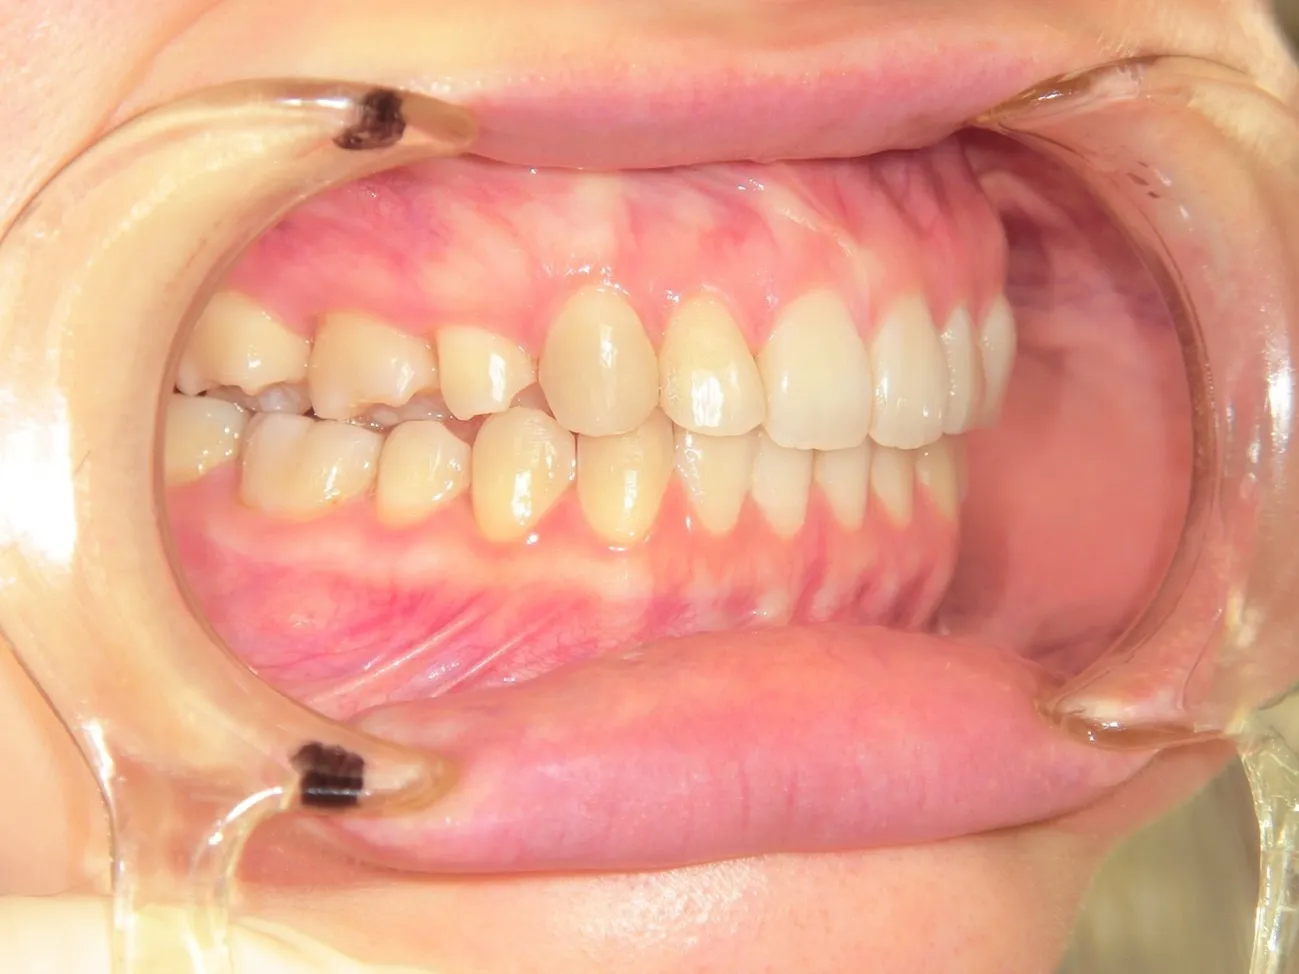

施術を検討されている方に様々なケースの施術前後の違いをご確認いただけるよう、インプラントやインビザラインでの矯正の症例を画像も用いて一覧にして載せております。「ずれている前歯を揃えたい」「受け口を直したい」「抜けた歯をキレイに整えたい」など、様々なご相談を承り、ご予算や仕上がりのご要望はもちろんのこと、長期的な口腔の健康維持も考慮したプランをご提案いたします。